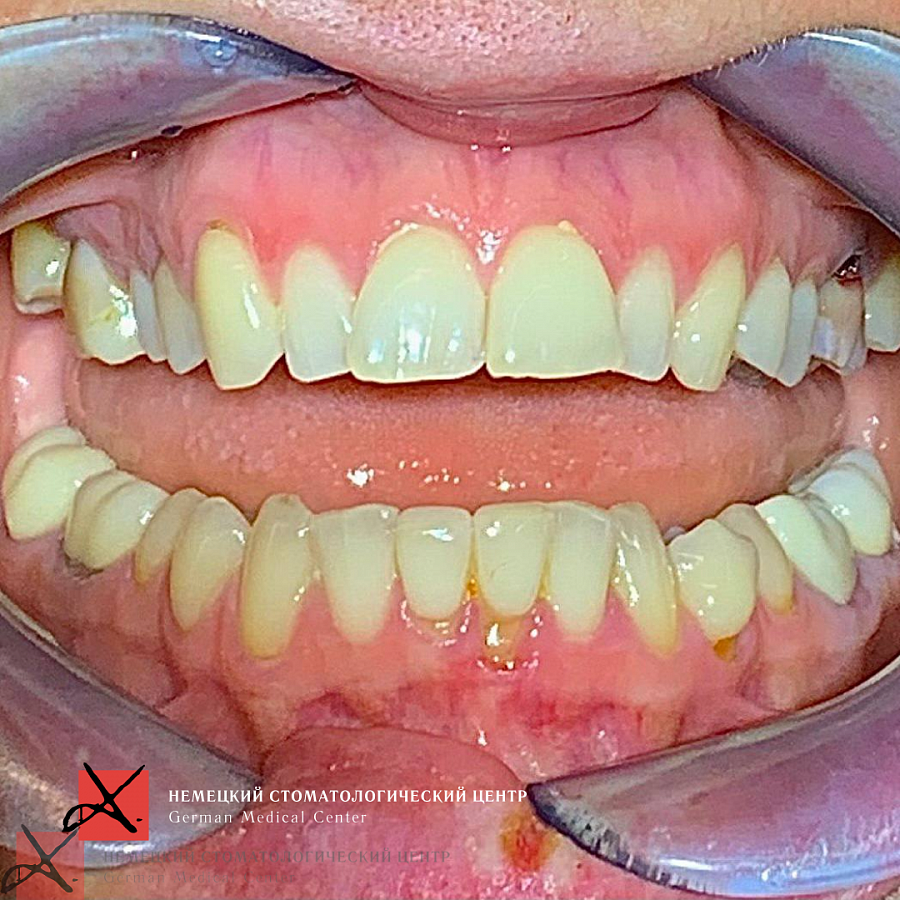

Обращение пациента

картинка

С какой проблемой обратился пациент

1. Жалобы на эстетический вид зубов.

2. Нарушение функций жевания.

3. Изменение контура лица.